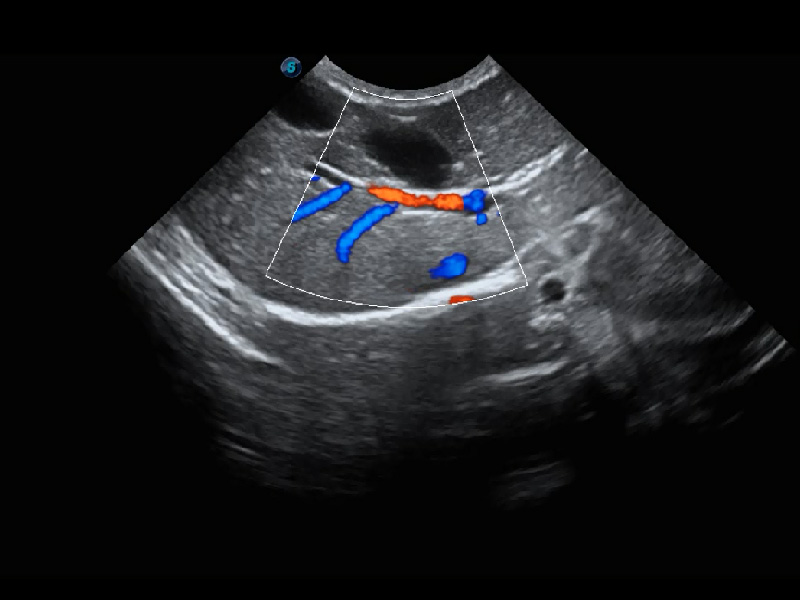

ProPet 60 作为一款高端台式动物超声设备,为动物医生的日常诊断提供了一系列贴合动物临床需求、解决临床实际问题的高级成像功能。凭借全系列高清探头,满足医生对腹部、心脏、生殖、浅表、肌骨等成像的所有需求,切实帮助您提升检查效率,提高诊断信心。

动物是人类最亲密的朋友和最值得信赖的伙伴。DB中国旗舰官方网站也一直致力于探索动物专用的超声影像解决方案。 全新推出的ProPet系列,是DB中国旗舰官方网站在动物超声影像智能化、专业化、精准化的一次跨越式革新。动物不能用言语来表述自己的不适,通过超声影像,ProPet系列搭建了动物医生与不同物种沟通的“桥梁”,为动物医生注入了“治愈之力”。